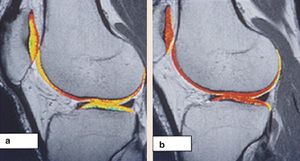

#dGEMRIC technique requires the use of Gd(DTPA)-2 as contrast agent. Why should we use only this type of contrast agent? This is a representative example from a study in which T1 mapping was done using (a) a charged contrast agent, Gd(DTPA)-2, and (b) an uncharged contrast agent, Gd-HPDO3A. The uncharged agent distributed uniformly, suggesting that the distribution of the charged agent is related to tissue charge.